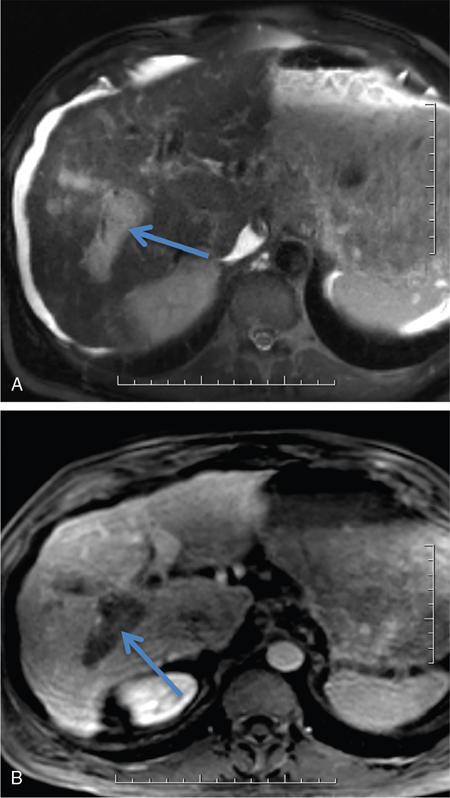

Ritu K. Kashikar, Shrinivas B. Desai, Payal Agrawal A spectrum of vascular variants can involve the liver. Both congenital and acquired anomalies can be seen. The abnormalities can involve the portal venous system, hepatic artery, hepatic veins or maybe the result of shunting between any of these vessels. Though not commonly encountered, familiarity with the pathogenesis and imaging features of these vascular entities can guide appropriate patient management. This chapter aims at classification of vascular pathologies of the liver (Table 9.12.1) with description of important entities. The umbilical vein accounts for approximately 80% of the afferent flow into the liver in utero. The umbilical vein joins the left portal vein, which in turn drains into the ductus venosus and carries blood to the inferior vena cava. The umbilical vein and ductus venosus start involuting at birth and typically close in the first week of life in term neonates (Fig. 9.12.1). Detailed embryology of the portal venous system has been discussed in previous chapters. The portal vein accounts for two-thirds of the hepatic blood supply. The distinctive feature of the portal vein is that it begins and ends in capillaries. The blood from the entire gastrointenstinal tract (except lower rectum), gallbladder, pancreas and spleen is carried via the portal vein to the liver. The hepatic arterial branches divide along the distribution of portal venous radicals and supply oxygenated blood to the sinusoids (Fig. 9.12.2). These include The dorsal and ventral limbs of the vitelline vein form the normal portal vein. Atrophy of the ventral limb occurs during embryogenesis. This maybe an incidental finding, though association with duodenal obstruction is seen in 50% cases. The aetiology of duodenal obstruction is often due to secondary causes such as duodenal stenosis, atresia, Ladd bands due to malrotation or annular pancreas. Associations include heterotaxy (polysplenia) and biliary atresia. Aberrant vessel may give an extrinsic impression on the high second portion of the duodenum on upper GI series. USG may show aberrant vessel in patients being scanned for other anomalies. The aberrant vessel is usually incidentally discovered intraoperatively during surgery for duodenal obstruction or malrotation. Hypoplasia or atresia of the portal vein may involve all or a portion of the portal vein. Atresia of a major branch is associated with absence of the corresponding hepatic lobe. Main portal vein hypoplasia or stenosis results in prehepatic portal hypertension and gastrointestinal hypertension (Flowchart 9.12.1). A portal vein smaller in calibre or as small as the adjacent hepatic artery is termed hypoplastic. The venous diameter in cases of hypoplasia is of 3 mm. Twenty-six per cent cases with biliary atresia have hypoplastic portal vein. TAPVR is a congenital cardiac malformation in which pulmonary veins instead of draining into left atrium during cardiac development, drain into the right atrium via an anomalous vein, resulting in right to left shunts. Types: In type 3 TAPVR an anomalous infradiaphragmatic vertical vein is formed by the confluence of pulmonary veins, typically through the oesophageal hiatus. Venous obstruction at the level of the diaphragm and accounts for the clinical presentation of pulmonary venous congestion and oedema. Early presentation (within 24–36 hours of life) included respiratory distress with cyanosis, tachypnea, and tachycardia. Features on X-ray include normal–sized heart with pulmonary interstitial oedema. One-third of patients have an additional complex cardiac anomaly and heterotaxy with right atrial isomerism. May show abnormal draining vein draining into the IVC or pulmonary vein. CT/MR venography allows accurate depiction of the anomaly. The pulmonary venous confluence drains to systemic veins below the diaphragm. The confluence is usually posterior to the left atrium and vertically oriented. From here, a descending vein passes through the oesophageal hiatus and most frequently drains into the connection in to ductus venosus, hepatic veins or inferior vena cava is not as frequent. Portosystemic shunts are classified into intrahepatic and extrahepatic. In the intrahepatic shunts, the shunt is at the level of PV branches after its division whereas in the extrahepatic shunts the anastomoses are between the tributaries of the portal or mesenteric system or main PV and a systemic vein (Flowchart 9.12.2). Abernethy malformation, also known as congenital extrahepatic portosystemic shunts (CEPS) is a rare clinical entity, in which portal blood is shunted partially or completely into the systemic circulation via an abnormal communication of the portal system with the systemic circulation. It results from persistence of embryonic vessels. The entity was named by John Abernethy in 1793. The embryological development of the portal vein occurs between the 4th and 10th weeks. The umbilical veins of chorionic origin, vitelline veins and the cardinal veins from the body of the embryo are the three paired venous systems seen in the embryo in the 4th week. Communications develop between the vitelline veins at 4 weeks, which anastomose to form a figure-of-eight configuration around the developing duodenum. Selective involution of these veins leads to the final configuration of the portal vein. Because the vena cava also has a complex development and is derived from several venous channels including the sinus venosus and a portion of the anastomosis between the right and left vitelline veins in the cranial part of the liver, it has been suggested that this may be the embryological basis of development of congenital extrahepatic portosystemic shunts. Various systems have been proposed for classification of Abernathy Syndrome: In this classification portal flow is classified as Patients with type A drainage show associated cardiac anomalies, while gastrointestinal bleeding is common in type C. In this system CEPS was classified into three types depending on the degree of severity of intrahepatic portal system hypoplasia in to mild, moderate and severe types. This system has therapeutic implications in providing information regarding acceptance of portal blood flow by the portal vasculature after shunt occlusion. CEPS may be asymptomatic well into adulthood and many authors have reported seeing adult patients presenting for the first time with clinical manifestations. Clinical features of portosystemic shunts may broadly be divided into: These include hepatopulmonary syndrome, metabolic dysfunction and hepatic encephalopathy. Patients with type 1 shunt have a female preponderance and often have concomitant congenital anomalies. These anomalies are less common in patients in type 2 shunts. Other anomalies have also been reported in patients with Abernethy malformation which include chromosomal anomalies such as Downs syndrome and structural anomalies of the heart, gastrointestinal, genitourinary, skeletal and vascular systems. Approximately half the patients of CEPS have nodular lesions of some sort in the liver (Flowchart 9.12.3). Nodular hepatic lesions in patients with congenital portosystemic shunts may be single or multiple. In order to establish a diagnosis of CEPS a communication between the portal and the systemic venous system, either before or after the formation of the PV by union of the SMV and SV has to demonstrated. Secondary causes of nonvisualization of the PV such as portal cavernoma or PV thrombus should be excluded. Patients with congenital portosystemic shunts do not have features of portal hypertension, such as splenomegaly, varices and collaterals. USG may demonstrate the shunt and show haemodynamics involved such as the magnitude and direction of flow. It may pick up congenital shunts preoperatively; however, it may not detect associated anomalies particularly of lung and heart. Smaller shunts, particularly type 1a may not be well picked up. Ultrasound may not fully characterize liver lesions seen in these patients. It is the modality of choice and can accurately diagnose the shunt and type and aids in management. Shunt is visualized as an abnormal communication between the portal venous and systemic circulation and is best depicted in the portal venous phase. CT also shows presence/absence of intrahepatic branches of portal vein. Evaluation of associated anomalies particularly in patients with congenital heart disease who require evaluation of pulmonary vasculature, or patients with suspected hepatopulmonary syndrome who require evaluation of the lungs can also be done with CT (Fig. 9.12.4 and Table 9.12.3). Another major advantage of CT is that it helps to detect and characterize hepatic lesions in these patients. It displays the arterial and venous anatomy, and provides an angiographic road map for surgical resection. Regenerative nodules are usually homogeneous with enhancement during arterial phase, on both CT, however without washout (Fig. 9.12.5). Rest of lesions show classic enhancement pattern as described in previous chapters. The imaging findings in patients with Abernethy malformation with hepatocellular carcinoma do not appear to be typical, that is hypervascularity on the arterial phase images with washout on delayed phase. Thus, patients who do not have typical findings of a benign lesion, that is lack of arterial enhancement, should be closely followed up or biopsied. Disadvantages of an MRI include longer periods of sedation which is a disadvantage in patients with CEPS who may be very young, very hypoxemic or encephalopathic. MRI also has lower spatial resolution than CT and may not show small intrahepatic portal venous radicles in type 2 patients. MRI can otherwise show all abnormalities seen on CT. Advantages of MRI using hepatobiliary contrast agents are in the characterization of hepatic nodules and for follow-up. MRI does not expose the patients to ionizing radiation. Patients with no symptoms, those with mild metabolic abnormalities and with liver nodules should be followed up with ultrasound and biochemistry. Patients with portosystemic encephalopathy, liver dysfunction or those with shunt ratio >60% should be treated according to type of shunt. Patients with type 1 shunts should be transplanted. Patients with type 2 shunts should be treated with shunt closure – either via embolization or surgical. Liver transplantation is considered when medical and surgical methods fail especially in patients with complications. Intrahepatic portosystemic shunts are rare. They may be congenital or result from trauma or portal hypertension. They develop due to persistent communications between vitelline and umbilical systems. These are communications between the branches of the PV and inferior vena cava (IVC). Park et al. classified these 1990 in four types. Type 5 was added later, these are classified in Table 9.12.4. Type 2 shunt with or without a focal varix is the most common type reported. Another classification system is proposed by Kanasawa et al. based on correlation with severity of portal hypoplasia (mild, moderate and severe) with portal venous pressure, histopathological findings, postoperative portal venous flow and hepatic regeneration. Associated anomalies such as cardiovascular, hepatobiliary, urogenital and gastrointenstinal can be seen. Complications such as portopulmonary hypertension are seen in 13%–66% children. As a consequence of long-term shunting, hepatic encephalopathy, and hepatopulmonary syndrome are the most common symptoms. Tumours such as FNH and regenerating nodular hyperplasia can be seen. These shunts may close spontaneously within the first 2 years of life or may remain asymptomatic and undetected for several years. When chronic shunting persists into adulthood, patients most often present with encephalopathy. The feeding (afferent) and draining (efferent) vessels of the shunt appear as enlarged, tubular, anechoic structures that are contiguous with the portal and hepatic veins. Antegrade flow is seen on colour Doppler images. Focal varix if present appears as an abnormal, rounded cystic structure with turbulent flow. Doppler study can also calculate the shunt ratio (total blood flow volume in the shunt divided by the blood flow in the portal vein). Shunt ratios greater than 60% should be corrected to prevent complications. Loss of normal undulating waveform of afferent portal vein branch with increased flow velocity and phasic waveforms owing to transmitted cardiac pulsations can be seen. The efferent hepatic vein branch of the shunt can show continuous flow with flattening of the Doppler waveform due to increased portal venous inflow. Communication between intrahepatic portal venous and peripheral hepatic venous radicals can be demonstrated easily on both contrast-enhanced CT and MRI. Similar to extrahepatic shunts CT is preferred over MRI in documentation of shunts. The afferent portal vein branch and the efferent hepatic vein branch are enlarged. Venous varices can be seen. The draining hepatic vein branch opacifies earlier than other hepatic veins (Fig. 9.12.6 and Table 9.12.5). The liver may show fatty degeneration and atrophy, but when the anomaly is corrected, fatty replacement disappears and liver size increases. Conservative medical therapy including restriction of protein and ingestion of lactulose. Symptomatic intrahepatic portosystemic shunts can be managed conservatively or with transcatheter embolization, surgical ligation or partial hepatectomy. The connection between the left umbilical vein and right hepatocardiac vein (future IVC) in the foetal circulation is called ductus venosus. This vessel is responsible for carrying nutrient-rich blood from placenta to the right atrium directly by bypassing the sinusoidal plexus of the liver. The umbilical vein and ductus venosus close at birth and form the ligamentum teres and ligamentum venous, respectively. The time interval following birth for closure of ductus venosus is variable ranging from few minutes after birth to 18 days in term neonates and as late as 37 days in premature infants. Patent ductus venosus is an intrahepatic portocaval shunt causing partial or complete diversion of portal blood to the systemic circulation and may present with hyperammonemia. Patent ductus venosus is seen on Doppler sonography as a vascular tubular structure in the left lobe of the liver, continuing from the umbilical vein and connecting the portal vein to the inferior vena cava. The foetal ductus venosus show waveforms similar to IVC corresponding to the cardiac cycle with a systolic and diastolic component. This diphasic waveform is seen in preterm and term infants and becomes monophasic as ductus closes. CT and MRI also accurately detect the shunt and patency. Associated hepatic lesions seen in patients with portosystemic shunts can be diagnosed and characterized better. Treatment (closure) is recommended in cases with complications or to prevent complications if the shunts persisted beyond 2 years of age. Shunt closure can be performed surgically or endoscopically. The complex nature of the shunt can pose problems during surgical closure. Transvenous and balloon occlusion have been done successfully. Occlusion of portal vein can occur due to a variety of conditions. The aetiologies of portal venous thrombosis in the neonatal age group include umbilical vein catheterization, omphalitis, dehydration or neonatal sepsis. Older children develop occlusion secondary to intraabdominal infections and portal hypertension. Other aetiological factors include prothrombotic states such as hereditary deficiency of protein C or protein S and factor V Leiden deficiency, vascular injury, trauma, stasis and congenital anomalies such as webs. Acute portal vein thrombosis can be asymptomatic, or the patient may present with abdominal pain, ascites or fever. Chronic portal vein thrombosis presents as ascites, encephalopathy, varices and upper gastrointestinal bleeding. Acute thrombus appears hypoechoic filling defect on USG with absent flow on Doppler. There is distension of the thrombosed vein (Fig. 9.12.7). CT and MRI with contrast will detect filling defect in the vein with distension. T2W1 images may show absence of flow void. Acute thrombus may appear hyperintense on T1W1 images. Tumour thrombus reveals signal similar to tumour on all sequences with diffusion restriction (Fig. 9.12.8). Chronic thrombus may present as eccentric filling defect, attenuation of vein or less commonly calcification of vessel wall. Collaterals are often seen in chronic portal vein thrombosis. Treatment usually involves combination of anticoagulation and intervention depending on age of thrombus. An acute portal venous thrombus may undergo partial or complete spontaneous resolution. The commonest cause of paediatric portal hypertension in the developing world is extrahepatic portal vein obstruction (EHPVO). It is also the second most common cause of portal hypertension in the western world. EHPVO is a condition characterized by obstruction of the extrahepatic portal vein (as the name suggests) with or without associated involvement of the intrahepatic branches, splenic vein (SV) or superior mesenteric vein (SMV). The hallmark of this chronic longstanding condition is carvernomatous transformation of the portal vein. Acute and chronic portal vein thromboses occurring in the setting of liver cirrhosis or HCC are not included in this disorder. EHPVO is an important cause of noncirrhotic portal hypertension with preserved liver structure and function till late in course of the disease. Proposed aetiologies include infection or prothrombotic event occurring early in life (in genetically predisposed individuals), leading to portal venous occlusion (Table 9.12.6).